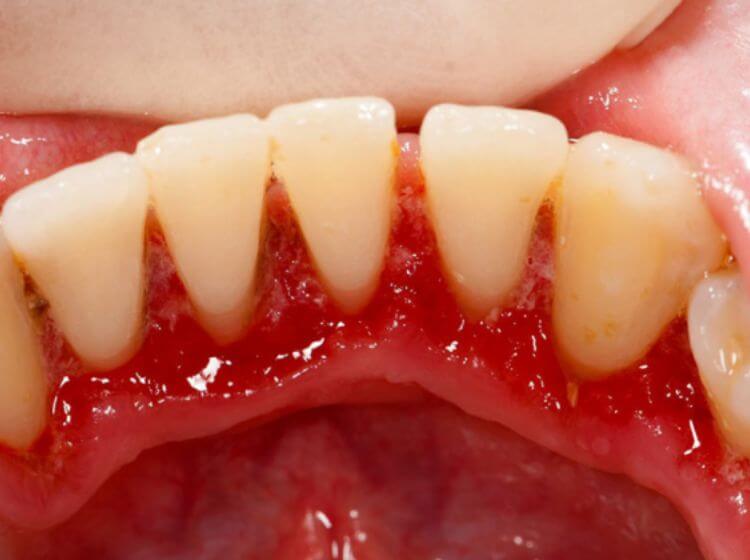

– Dễ bị chảy máu lợi: Đây là dấu hiệu thường gặp khi mắc bệnh viêm lợi răng. Ngoai ra, có thể xảy ra tình trạng chảy máu lợi khi đánh răng, dùng chỉ nha khoa hoặc thậm chí là lúc ăn uống.

– Lợi có màu đỏ sẫm hoặc tím: Lợi khỏe mạnh có màu hồng nhạt. Khi bị viêm, lợi sẽ chuyển sang màu đỏ sẫm hoặc tím.